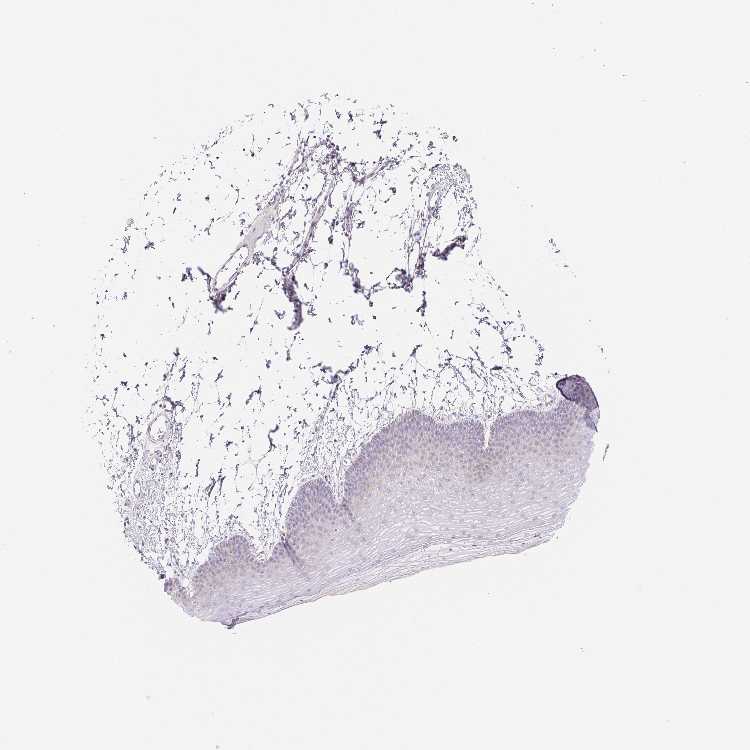

SKIN 2 - Antibody stainingi

Antibody staining in the annotated cell types in the current human tissue is reported as not detected, low, medium, or high, based on conventional immunohistochemistry profiling in selected tissues. This score is based on the combination of the staining intensity and fraction of stained cells.

Each image is clickable and will lead to virtual microscopy that enables deeper exploration of all samples and also displays staining intensity scores, fraction scores and subcellular localization as well as patient and tissue information for each sample.

Antibody HPA059150

Epidermal cells Not detected